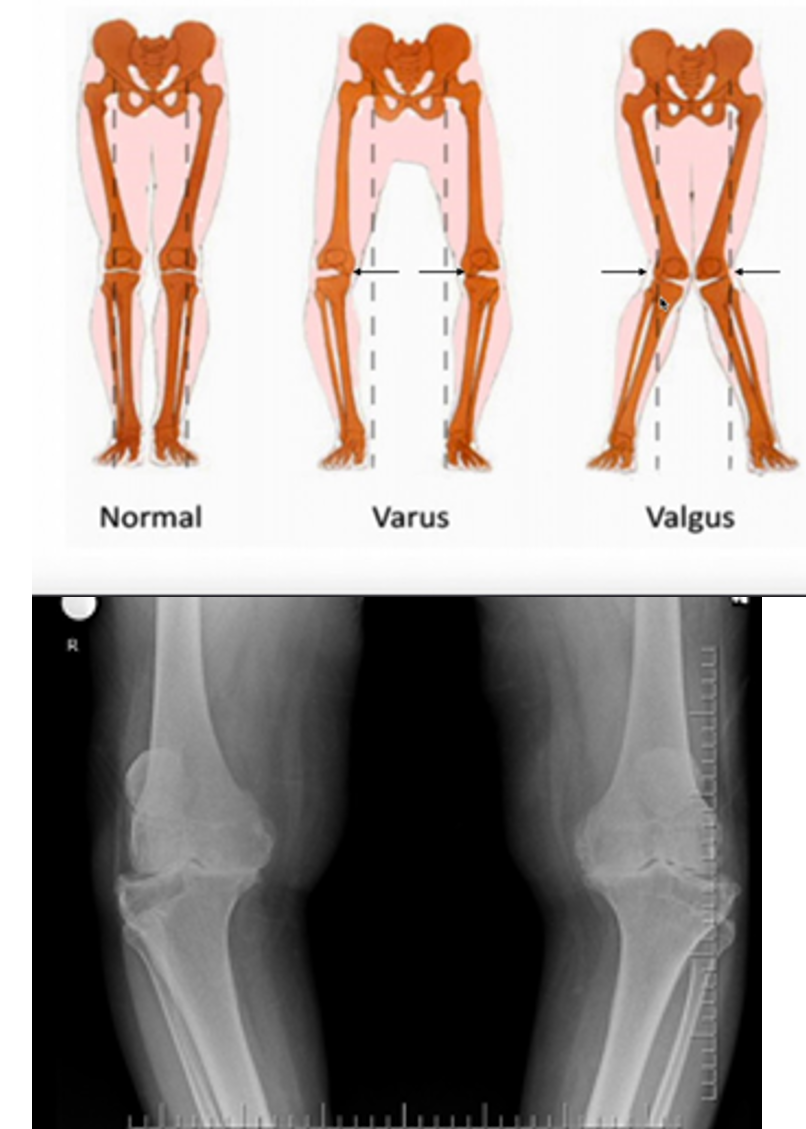

Degenerative Joint Disease/Arthritis PE

• Inspection

• Body h______

• G____ (often protects the affected side)

• Ef_____?

• Alignment

• Va___ or Va____?

• Range of motion (compare to _____lateral side)

• ______ exam (stiffness of arthritis usually precludes any significant issues with ligament laxity)

A

• Body habitus

• Gait (often protects the affected side)

• Effusion?

• Varus or Valgus?

• Range of motion (compare to contralateral side)

• Stability exam (stiffness of arthritis usually precludes any significant issues with ligament laxity)